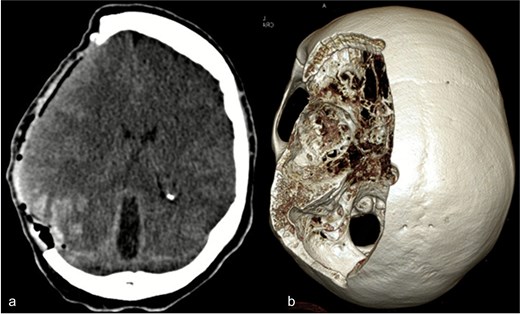

Due to elevated intracranial pressure caused by subdural and subarachnoid hemorrhage, an osteoclastic craniotomy was performed to evacuate the hematoma and relieve pressure (Fig. 2a and b). A large volume of blood was released during trepanation, necessitating intraoperative blood transfusion. Injury to the superior sagittal sinus during the procedure resulted in significant bleeding (Fig. 3), which was managed pharmacologically with the administration of clotting agents. The excised bone flap was sent for histological analysis, which was negative for bacterial infection.

(a) Axial CT image after osteoclastic craniotomy and (b) in the 3D reconstruction representation of the large bone defect.

Postoperative axial CT scan. After osteoclastic craniotomy, a large bony defect with parenchymal hemorrhage and additional hemorrhage in the right parietal region is evident.